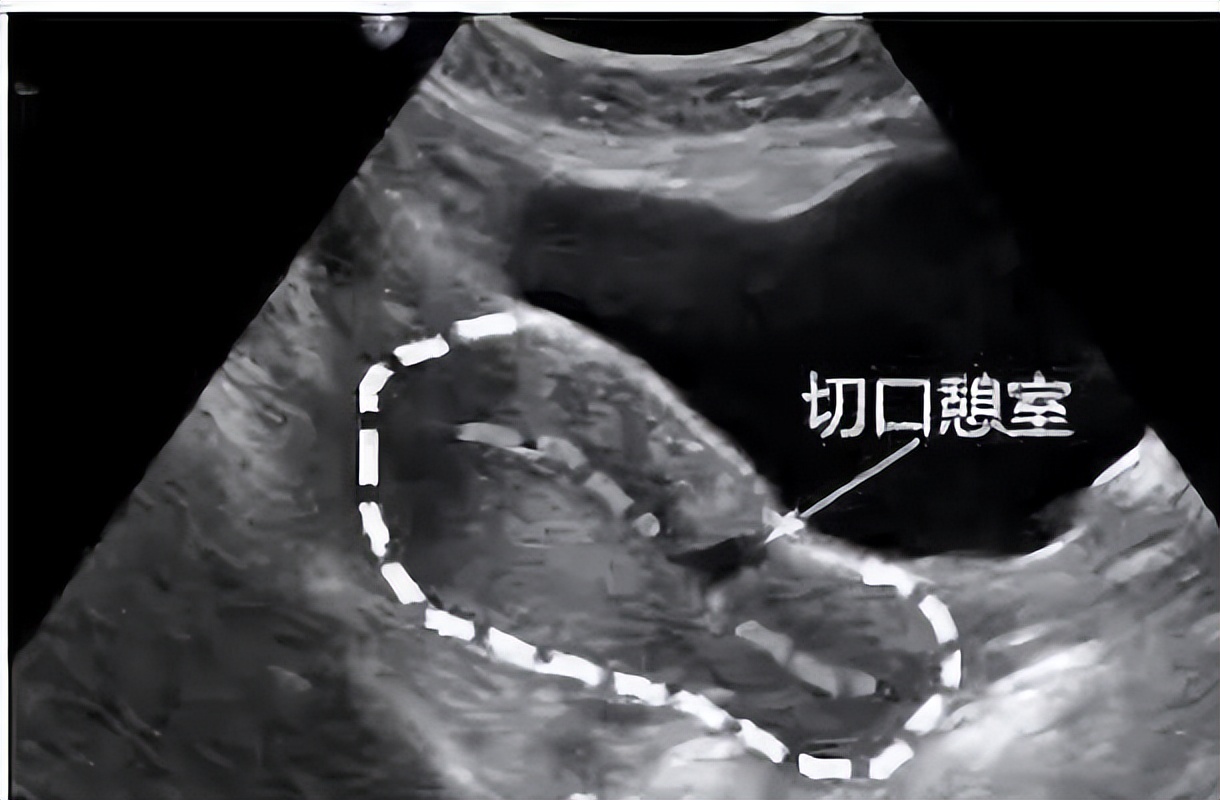

对于手术,我们老百姓有个俗称,叫「开刀」。既然是开刀自然会有一个切口,当剖宫产术后的子宫切口愈合缺陷时,切口处会出现一个与宫腔相通的凹陷,看起来好像一道沟,这个凹陷就是我们所说的憩室。

剖宫产术后子宫切口憩室 (previous cesareanscar defect,PCSD )以往报道较少 ,1955 年西班牙学者首次报道了子宫切口憩室。由于它是在剖宫产后出现,所以被称为剖宫产术后子宫切口憩室,又俗称为剖宫产瘢痕憩室。

子宫切口憩室多位于子宫下段或峡部,少数位于宫颈上段,主要与原剖宫产切口部位及剖宫产时临床宫颈有无缩短或扩展有关,简单点说,它就像一间违章改建的“危房”。